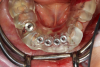

Fig 42. Occlusal view of prepared implants.

Figure 42